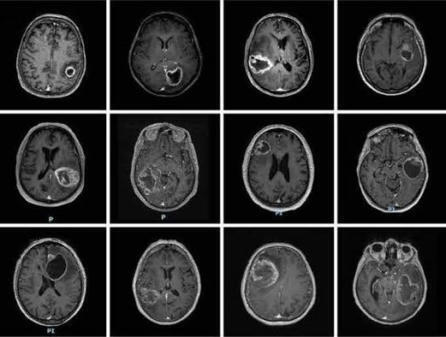

Glioblastoma (GBM) is the most common high-grade primary malignant brain tumor, characterized by a notably poor prognosis. Current treatments for GBM have shown limited effectiveness in improving patient survival, highlighting the urgent need for effective therapeutic strategies. Combination therapy offers significant potential in overcoming resistance by targeting multiple signaling pathways; however, it often comes with increased toxicity compared to monotherapy. Co-encapsulating multiple therapeutic agents into a tumor-targeted drug delivery platform holds promise for overcoming these limitations and improving treatment outcomes.